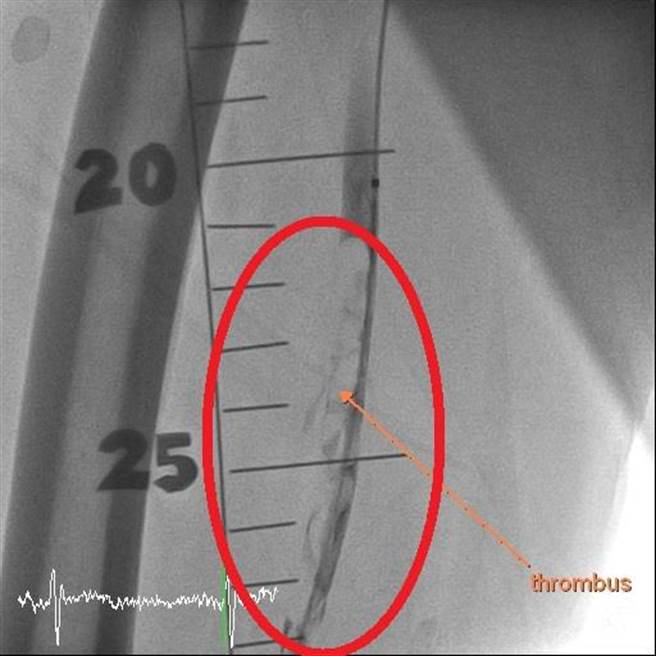

经微创喷射机械除栓手术,搭配导管溶栓治疗,成功打通陈爷爷右脚的血管。(大千医院提供/谢明俊苗栗传真)

杨智钧指出,过去传统治疗方式为使用药物及开刀清除血块,但出血风险很高,现行新技术「喷射机械除栓」设备,可以用微创的方式伸管子到血管里把血块清乾净,再搭配药物辅助,较传统治疗安全、成功率也较高。